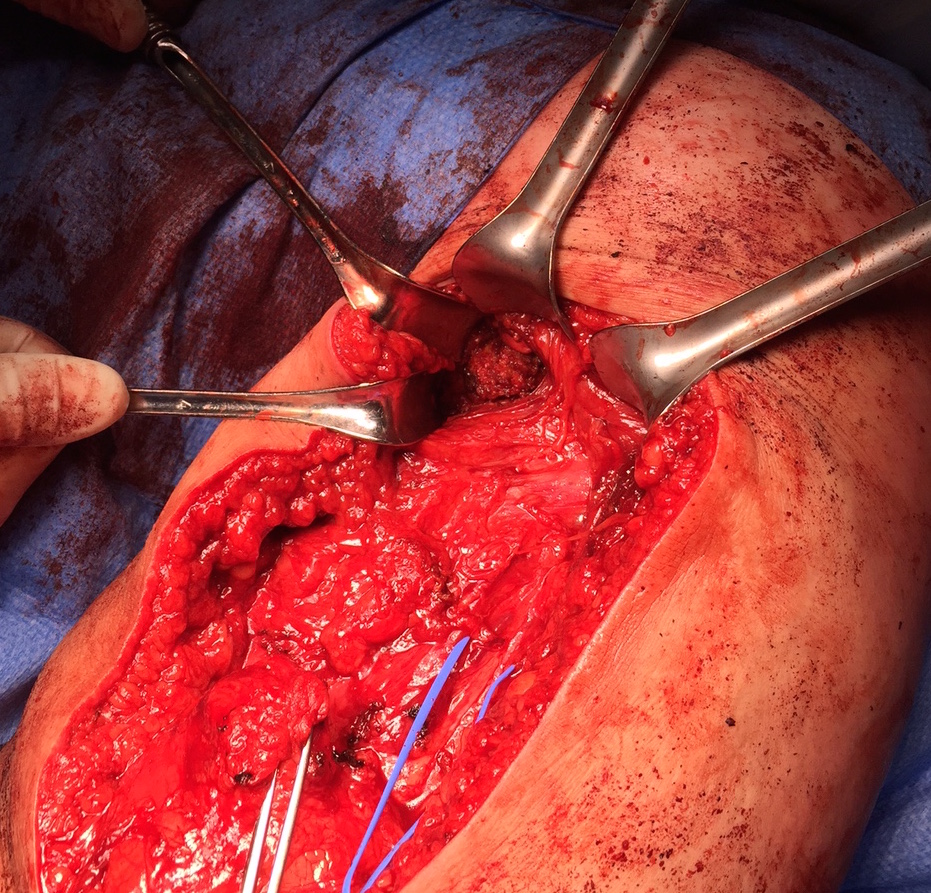

Expose ischial tuberosity

- superior retractor on ischial tuberosity

- medial and lateral retractors, care with sciatic nerve

- use osteotomes to create bleeding

Exposing ischial tuberosity (*) with Cobb retractor